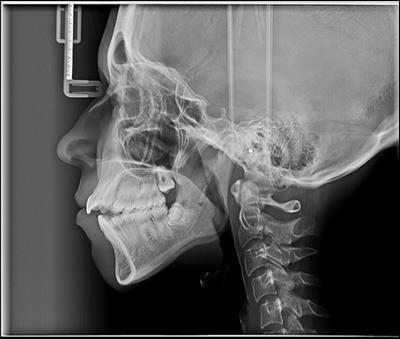

The cephalometric analysis indicated that she had a skeletal class II profile ,proclination of the maxillary central incisor ,high mandibular plane angle that contributed to the class II skeletal relationship and increased lower facial height.

Figure 2.Pretreatment cephalometric film